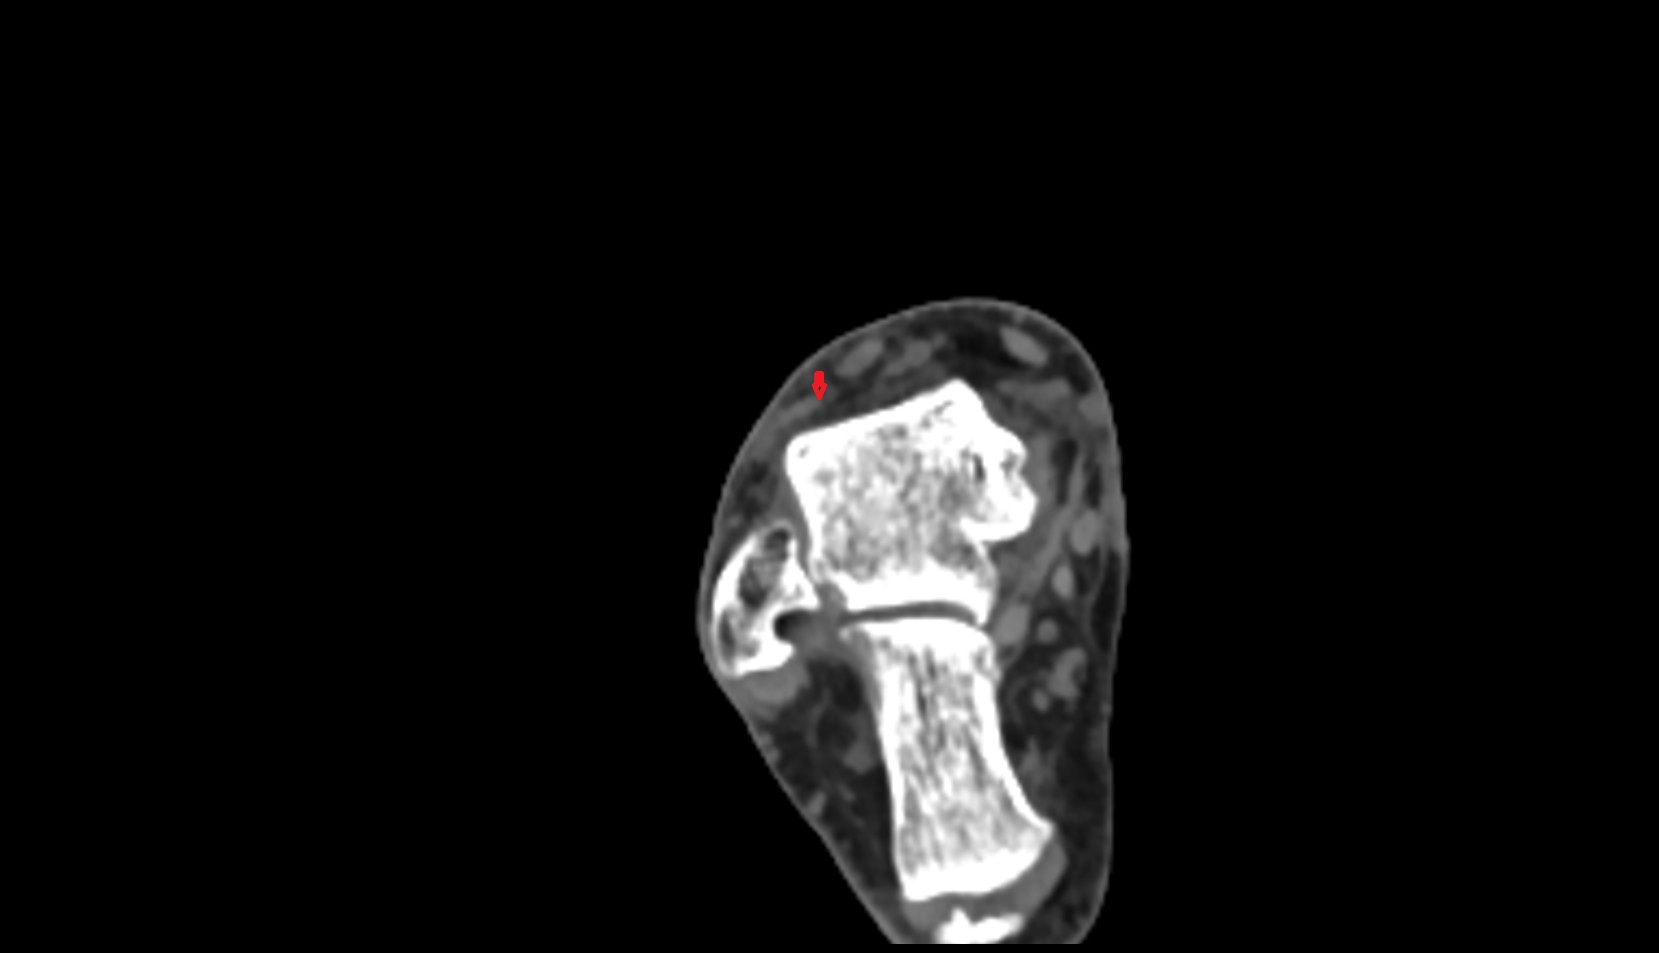

- Temporomandibular joint

- Mandibular condyle

- Mandibular fossa

- Mandible

- Neck of mandible